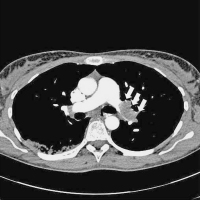

Verlaufskontrolle

Abbildung 3: CT-Verlaufskontrolle nach 6 Monaten mit nun freier zentraler pulmonalarterieller Strombahn (Pfeile).